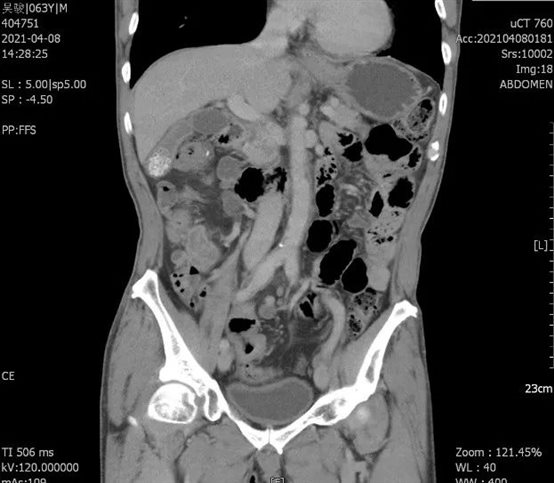

该患者因“排便习惯改变2月余,加重2天”收入我院消化内科,积极对症治疗后行结肠镜发现:距离肛缘18cm直乙结肠可见一巨大5*6cm肿块,占肠腔一圈,导致管腔狭窄,无法继续进镜。病理提示:腺癌。经会诊后转入普外科,术前检查评估,直乙结肠癌(cT3N1M0),同时发现升结肠肝曲处结肠壁增厚,恶性肿瘤可能,炎症不能除外。针对结肠肝曲恶性占位不能排除,杨孙虎主任提出了缜密的手术方案和计划。手术如期进行,术中探查结肠肝曲肿物,约5*4cm大小,质硬,冰冻,提示:腺癌。确定是多原发性大肠癌,杨孙虎主任决定一次手术完成两个肠段的根治性治疗。